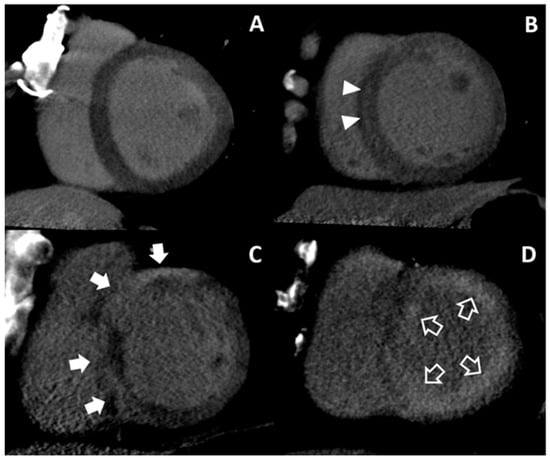

On DECT, inter-observer agreement was excellent for assessment (κ = 0.806) (Table 2). Afterwards, the observers concluded that MDE was observed in 41 patients (65.1%, 41/63), with infarction in 15 patients (23.8%, 15/63) and nonischemic patterns in 26 patients (41.3%, 26/63) in a consensus reading. Twenty-two patients showed no MDE (Group I). For the 15 patients with infarction (Group II), nine patients demonstrated multifocal subendocardial and transmural MDE at multi-vessel territories, five showed subendocardial or transmural MDE at the left anterior descending coronary artery territory, and one showed transmural MDE at the right coronary artery territory. For the nonischemic patterns, seven patients showed midwall MDE at the basal septum, four showed patchy MDE at basal junctions and three showed both patterns (Group III). In addition, 10 patients showed multifocal epicardial and/or patchy MDE (Group IV), and two showed global subendocardial MDE (Group V).

Eighteen patients of Group I and 14 patients of Group III had dilated cardiomyopathy. One patient of Group I showed significant 1-vessel disease on CCTA but was not regarded as ischemic HF because the diseased vessel was in the left circumflex artery without perfusion defect. Other patients with tentative diagnosis of dilated cardiomyopathy did not show significant CAD on CCTA. Eight patients of Group IV were supposed as having sarcoidosis or myocarditis without significant CAD on CCTA. One patient of Group IV was diagnosed with arrhythmogenic right ventricular cardiomyopathy because of multifocal low attenuations which did not correspond to the vascular territory at both ventricles on cardiac CT. One patient of Group I and one patient of Group IV were diagnosed as isolated LV noncompaction with prominent trabeculations according to the diagnostic criteria of non-compacted-to-compacted thickness ratio >2.3 [27]. For two patients of Group V, amyloidosis was considered. Although one patient with presumed amyloidosis had significant 1-vessel disease on CCTA, ischemic HF was not considered because of moderate stenosis in the left circumflex artery. Representative cases of nonischemic HF are shown in Figure 3.

Figure 3. Representative cases of nonischemic heart failure. No MDE is noted on the LV (Group I) (A). Ill-defined midwall MDE (arrow heads) is presented in the mid LV septum (Group III) (B). Multifocal epicardial MDEs (arrows) are noted in the basal septum (Group IV) (C). Global subendocardial MDE (open arrows) is demonstrated along the LV (Group V) (D). LV = left ventricle, MDE = myocardial delayed enhancement.